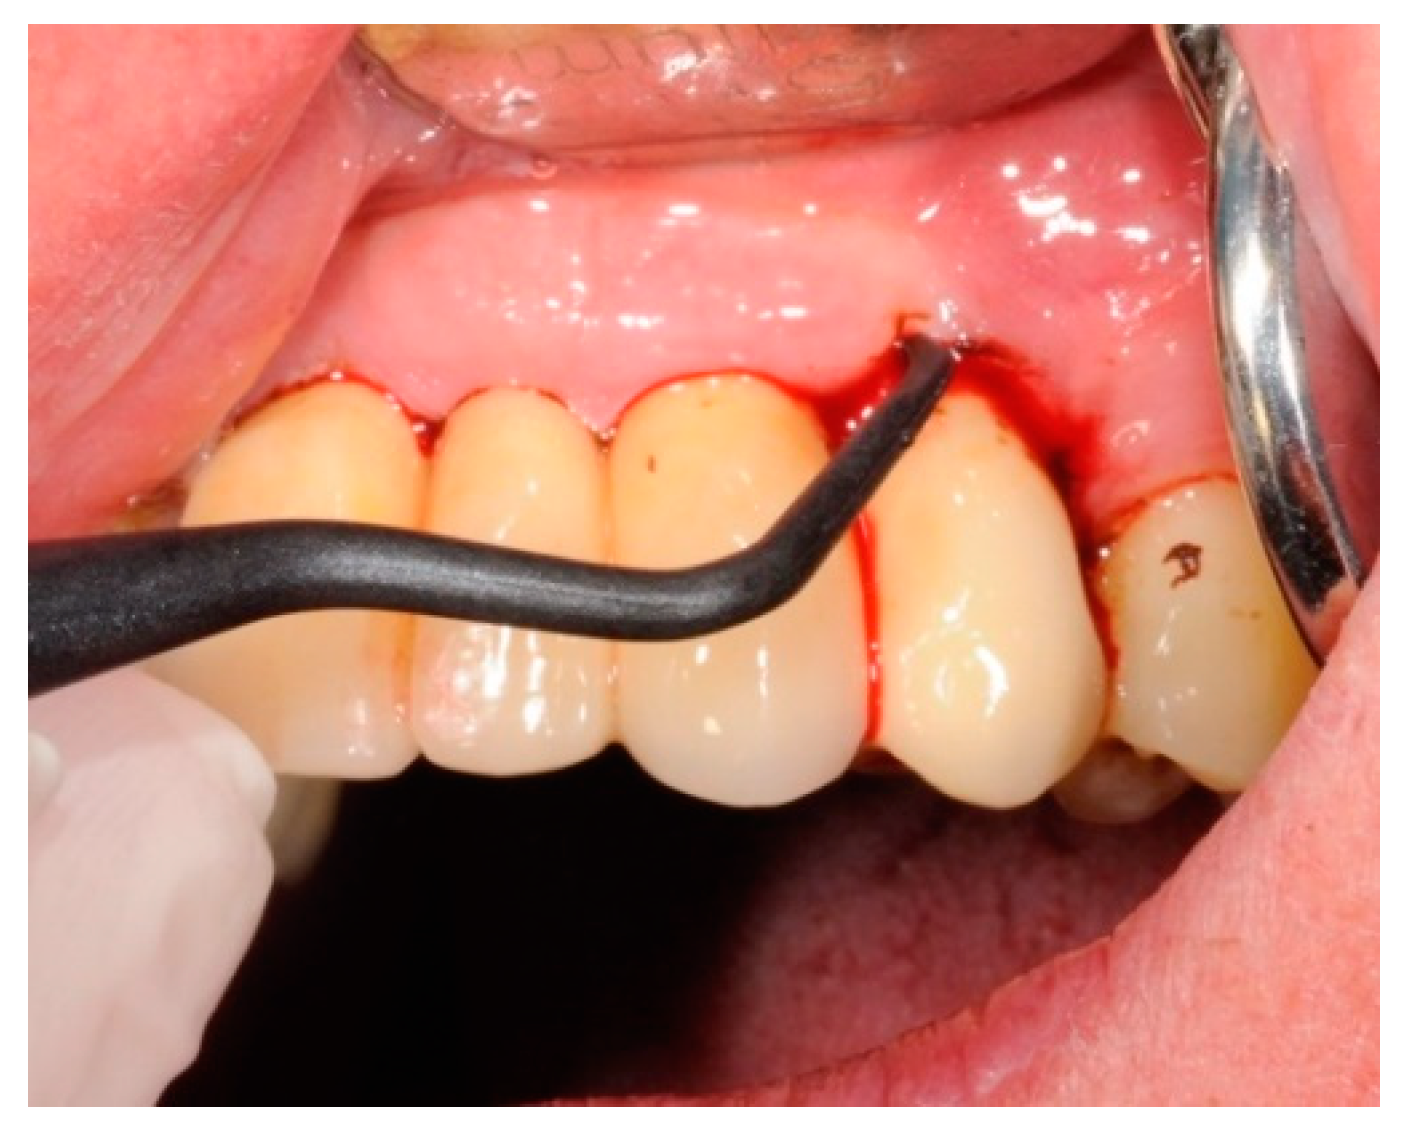

4.4. Study Protocol and Treatment

4.5. Test Substances and Administration